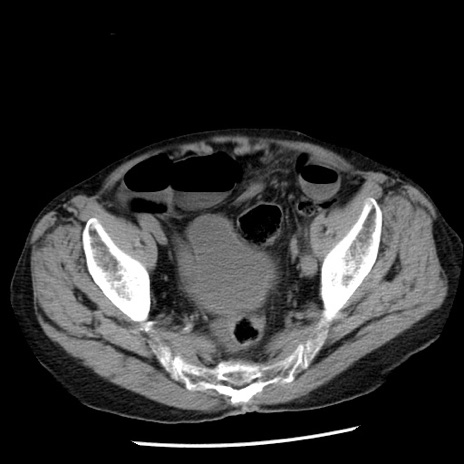

症例26(横断像)

【症例】80歳代男性

【主訴】嘔吐

【現病歴】昨晩2回嘔吐あり、今朝になっても嘔吐あり。来院。

【既往歴】胃潰瘍

【身体所見】意識清明、BT 37.6℃、BP 166/95mmHg、HR 100bpm、SpO2 97%、腹部:平坦・軟、腸蠕動音聴取良好、圧痛なし。

【データ】WBC 21900、CRP 1.46